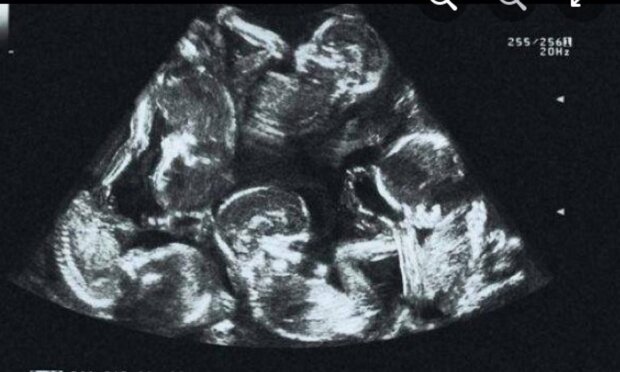

Kiedy para zdecydowała się na kolejne badanie ultrasonograficzne, odkryli, że Alexandra nie spodziewa się bliźniąt, a pięcioraczków! To zaskakujące odkrycie wywołało w niej lawinę uczuć, od radości po obawę i niepewność.

Gdy zbliżał się termin porodu, para udała się na kolejne badanie, aby upewnić się, że wszystko jest w porządku. Wtedy wyłoniła się prawdziwa prawda. Okazało się, że na świat przyjdzie nie pięcioraczki, a pięcioro dzieci! Ta niespodziewana wiadomość spowodowała u Aleksandry łzy wzruszenia. Jej emocje w tamtym momencie musiały być niezwykle silne, a szczęście i strach mieszały się w jedno.